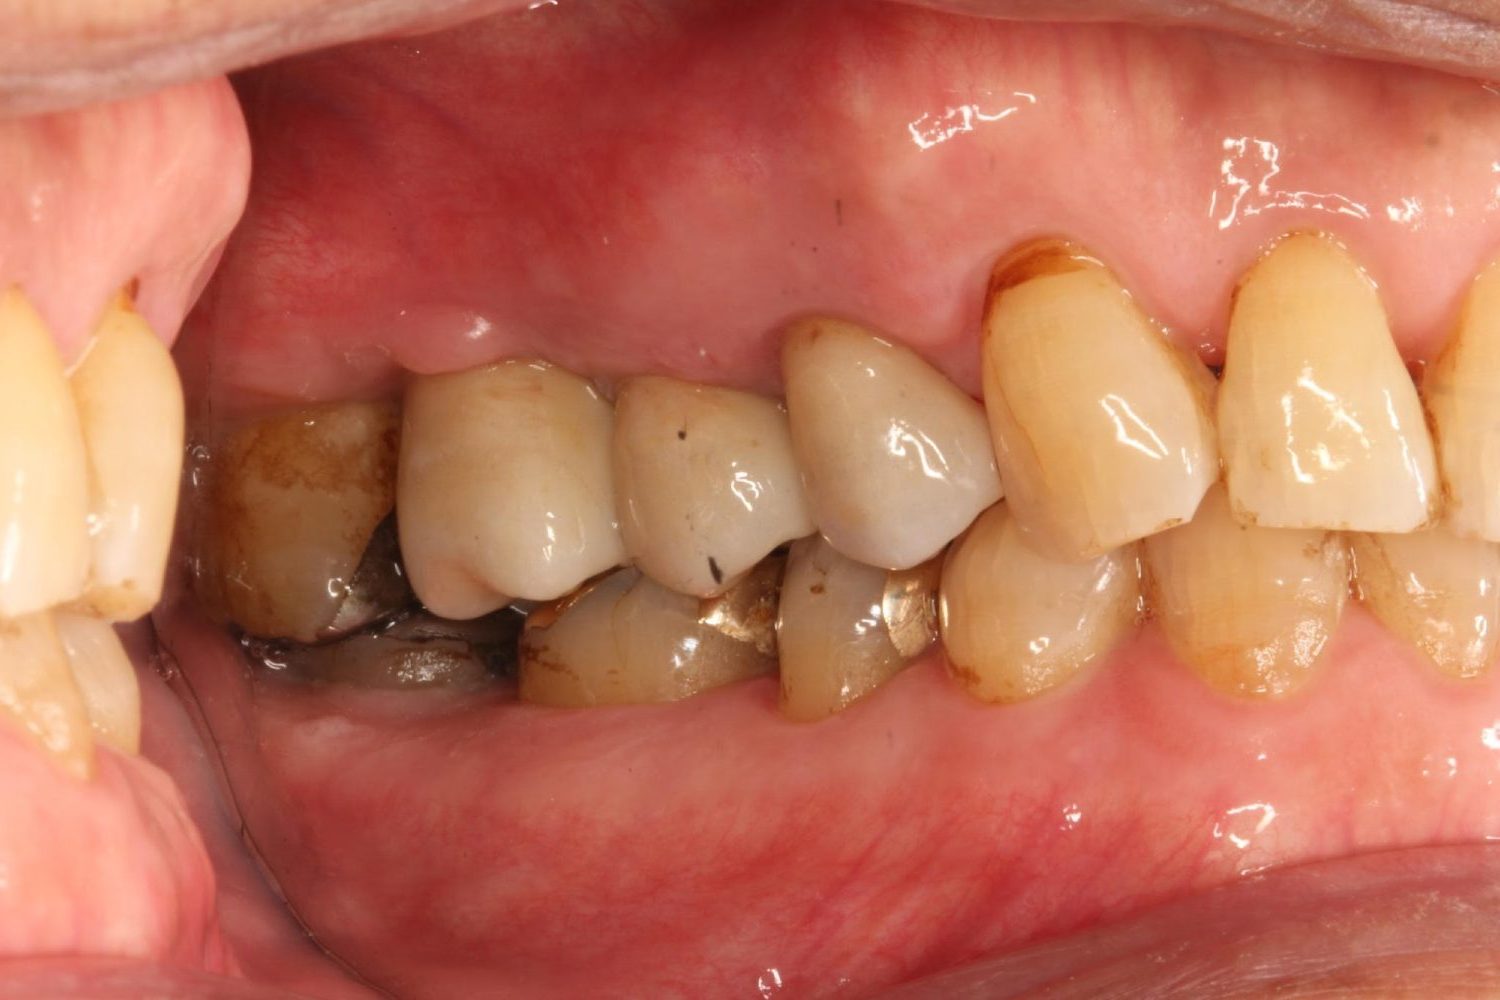

インプラント治療の症例紹介④

Before

After

主訴

義歯による疼痛

治療内容

下顎舌側に骨隆起があり義歯困難な状態。保存不可能な歯の抜歯を行い、インプラントを埋入し咬合再構成を行った。

治療費

2,851,200円(税込)

治療期間

29ヶ月

通院回数

26回

想定されたリスク

※咬合力の強い方なので、予防的にマウスピースの装着が必要。インプラント周囲炎の恐れがありました。

歯の欠損の対合歯の挺出等を修正し咬合平面を揃え咬合再構成を行った症例。